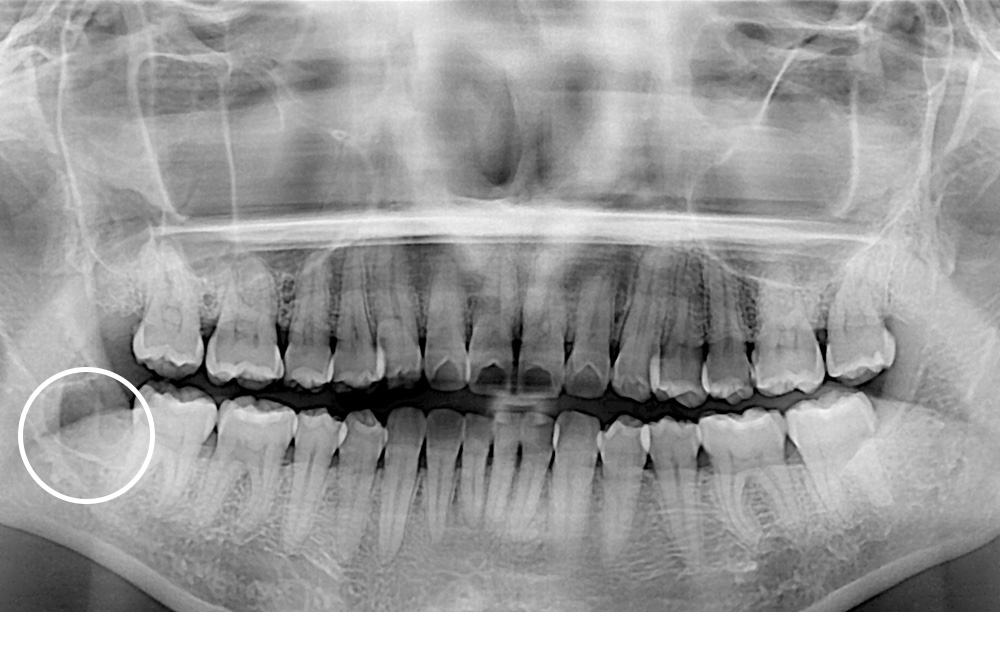

[사랑니] 매복 사랑니 발치

치료전 : 2021-07-02

세종치과는 구강악안면외과학 박사이신 원장님이 발치하는 치과입니다.